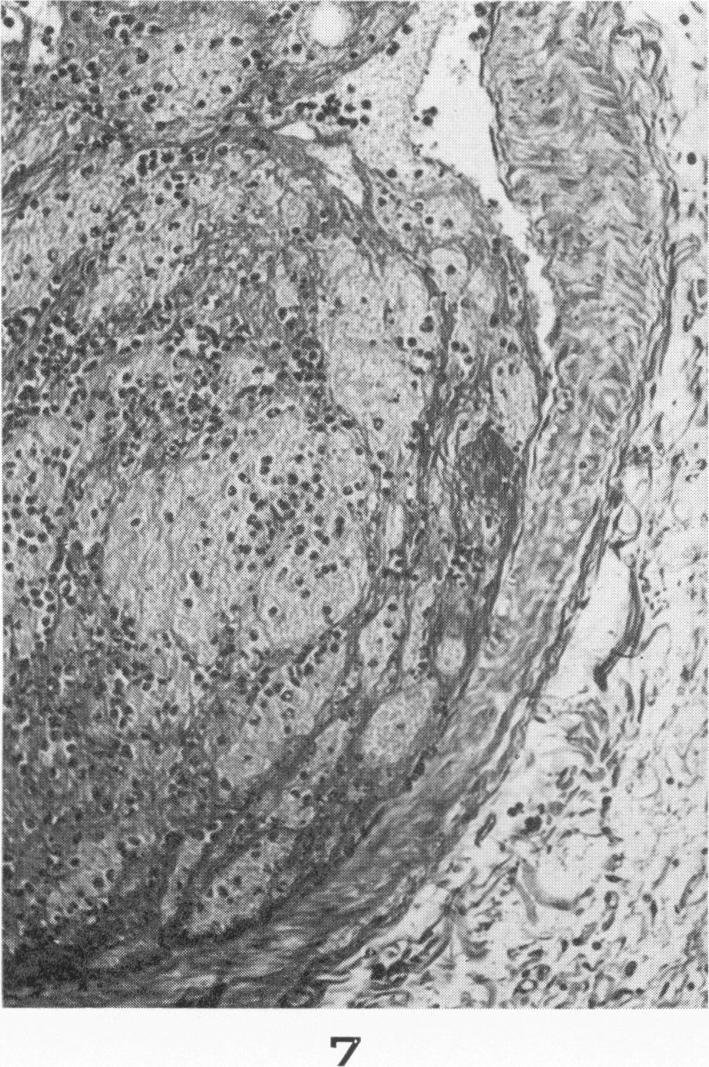

Chyme emboli in the lungs of goats wounded by missiles.

Am J Pathol. 1956 Jul-Aug;32(4):831-43.